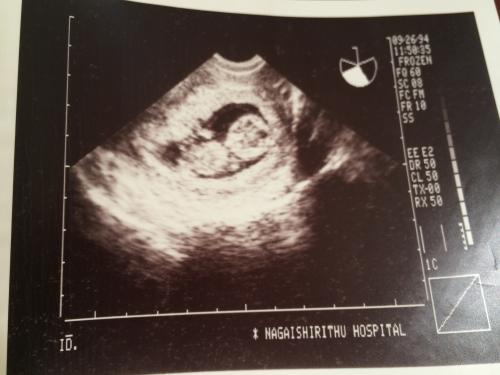

▼思い出の1枚……

みなさま、今日もたくさんのメッセージありがとうございました。リスナーさんの、思い出の1枚はオメデタの時のエコー写真というメッセージを聞いて そうだそうだ!と思い、早速 家に帰ってアルバムから引っ張り出してきました。こんなに小さかった我が子も 今や大学生……生まれた年は阪神淡路大震災の年……そして今日は東日本大震災から5年目……まだまだ避難生活を余儀なくされていらっしゃる方も多いと聞きます。そして、大切な命を失った方へ……今日は1日、祈りを捧げたいと思います……思い出の◯◯、思い出の1枚ひるらじ、ゆうらじにもメッセージお待ちしています!